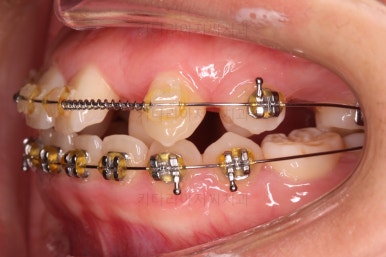

우선 장치를 저희 키다리아저씨치과에서 사용하는 장치로 바꿔 부착을 했어요.

세라믹에서 메탈로 안좋아진 것 아닌가요?

왼쪽이 처음 내원하셨을 당시의 입안 모습이고요. 오른쪽이 장치를 바꿔 부착한 이 후의 모습이에요.

세라믹에서 메탈로 다운그레이드 된 것처럼 보이죠?

사실은 훨씬 좋아진 장치랍니다.

유심히 보시면 왼쪽은 철사를 장치와 연결시키기 위해서 노란색 고무줄로 일일이 묶어줘야 하는 타입인데 비해, 오른쪽은 철사를 묶는 고무줄이 안보이죠?

바로 "자가결찰장치"라고 해서 브라켓에 일일이 뚜껑이 달려 있어서 철사를 장치 스스로가 직접 잡아주는 타입이에요.

그래서 메탈이라고 다 예전장치가 아니라는거죠.

메탈이라고 모두 예전 장치가 아니고 세라믹이라고 모두 최신 장치가 아닙니다.

자가결찰이 예전 장치에 비해 장점이 훨씬 많아서 아무리 세라믹이라고 한들 자가결찰 메탈이 훨씬 좋은 장치에요.

자가결찰 중에서도 재료가 메탈이 있고, 세라믹도 있어요.

(자가결찰 메탈, 자가결찰 세라믹 등)